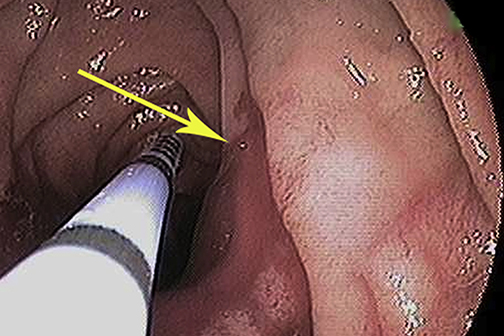

Study Finds Treating Precancerous Growths in People with HIV Reduces Anal Cancer by More Than Half

A team of researchers, including LSU Health New Orleans Infectious Diseases and Microbiology professor Michael Hagensee, MD, PhD, has shown for the first time that treating precancerous anal growths called high-grade squamous intraepithelial lesions (HSILs) in persons living with HIV significantly decreased the progression to anal cancer. Results are published in the New England Journal of Medicine. More